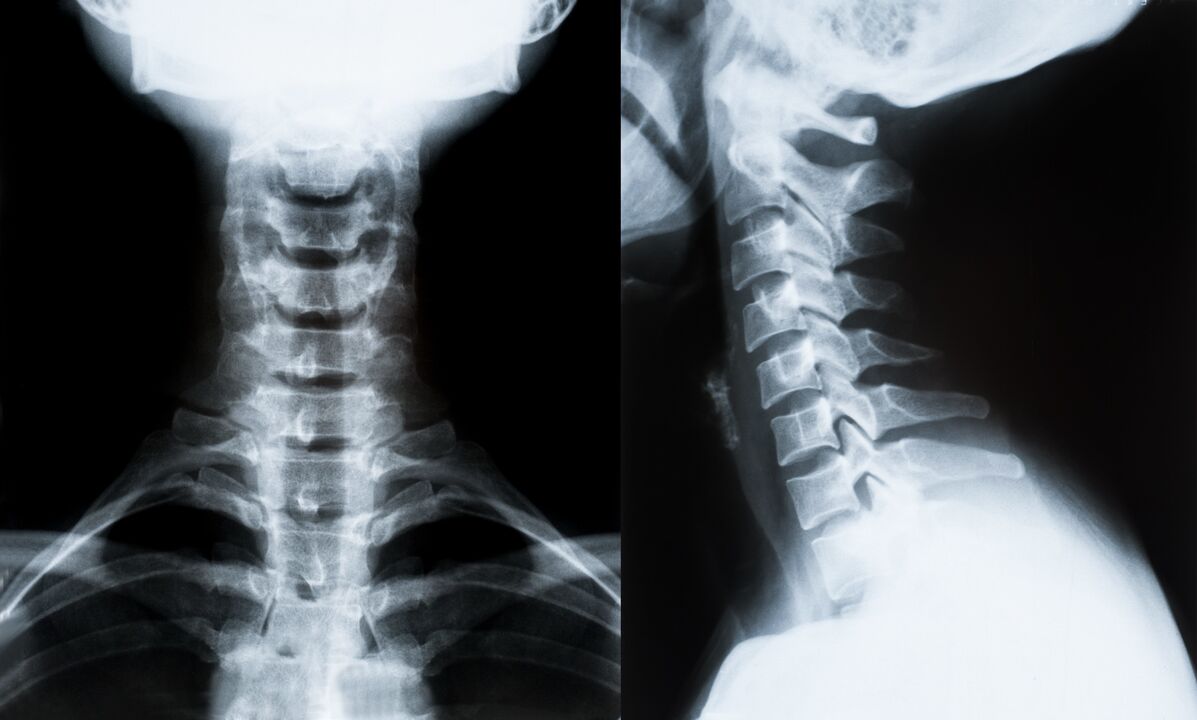

Hlavné metódy diagnostiky a ďalšieho určenia liečby osteochondrózy krčnej chrbtice:

- röntgen. Najmenej účinná, ale tradičná diagnostická metóda.

- Magnetická rezonancia je najúčinnejšou diagnostickou metódou. Pri tomto type vyšetrenia pacienta sú viditeľné všetky potrebné štruktúry.

- Ak je potrebné merať zmeny, používa sa počítačová tomografia. Určuje prítomnosť hernií a iných vecí.

- Poslednou metódou je ultrazvukové duplexné skenovanie. Táto metóda výskumu určuje rýchlosť prietoku krvi v tepnách.

Je nemožné presne určiť ochorenie chrbtice doma.